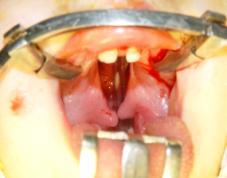

supramaxillary non-removable orthodontic appliances (Fig. 4). Others 17 children

with such pathology used the microimplants as supporting elements of

orthodontic appliances (Fig.5).

Fig. 5 -

patient V-yev, 5 months., bilateral

congenital cleft lip and palate after installation of the microimplants to the

upper jaw fragments and to the intermandibular bone

for orthodontic treatment.